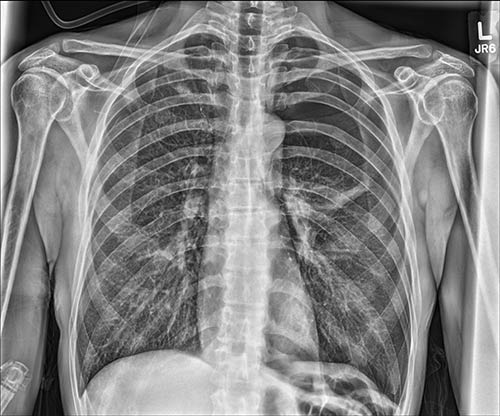

通过气胸可视化处理节省时间。它从原始曝光中生成一个相配影像,经过优化以突出呈现胸腔中的游离空气,提高诊断准确性并增强患者护理。